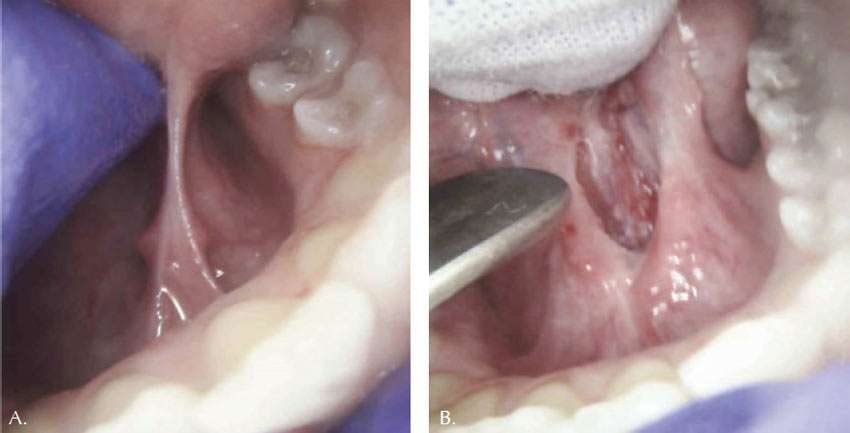

A fifteen-year-old autistic female with Turner syndrome was a patient who had required hospital admission for treatment of dental caries under general anesthesia due to her combative behavior and extensive caries since age 11. She had always been a gagging patient with oral aversion to any dental care. Her latest exam revealed a previously unrecognized restrictive tongue frenum, which was thought to be a source of her oral aversion and gagging (Figure 2A shows the thick and fibrous lingual frenal attachment). Since becoming more knowledgeable about apnea and the potential impact of the restrictive lingual frenum on the airway, Dr. Kaplan’s ability to diagnose this previously overlooked tongue-tie associated issue has improved. He was able to recognize the thick and short tongue frenum and consider surgery as a possible treatment to improve not only the reported pattern of restless sleep and snoring, but also the enhanced gagging reflex.

Immediately after the lingual frenectomy procedure was completed, tongue mobility was increased (Figure 2B). The two-week followup confirmed a better sleeping pattern, no more snoring and noticeable improvement in temperament, as reported by her mother. In addition, the patient was now less flatulent, likely indicating an improvement in swallowing mechanics. Treatment was accomplished due to the clinician’s ability to manage this patient in the least threatening and safest outpatient environment. The sedation, although never without risks, was the safest way to attempt treatment and obtain desired clinical results.